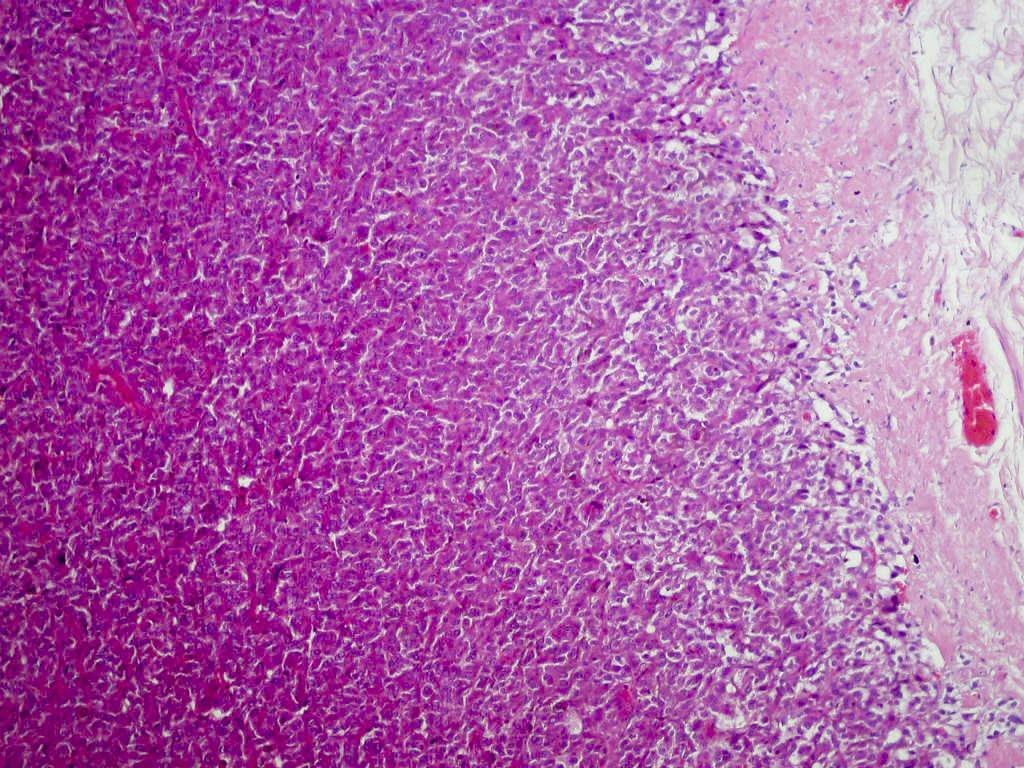

- Classic histologic morphology: monomorphic cells with abundant eosinophilic / amphophilic cytoplasm arranged in a nested / zellballen pattern and separated by fibrovascular septa with sustentacular cells

Microscopic (histologic) description

- Typical morphology: epithelioid cells with abundant, eosinophilic / amphophilic, granular cytoplasm and round / ovoid, vesicular / salt and pepper nuclei, arranged in a nested / zellballen pattern and separated by fibrovascular septae with sustentacular cells (Am J Surg Pathol 2004;28:94, World J Clin Cases 2014;2:591, Endocr Pathol 2022;33:90)

- May have focal pleomorphism, nuclear hyperchromasia, low mitotic activity or clear cytoplasm

Microscopic (histologic) images

Contributed by Theodorus H. van der Kwast, M.D., Ph.D., Michelle R. Downes, M.D., Debra L. Zynger, M.D. and David Cohen, M.B.B.Ch., M.D.

- Microscopic description: This specimen shows an unencapsulated, monomorphous population of round tumor cells in a nested / zellballen pattern with delicate vascular septa and intervening extravasated red blood cells. It predominantly involves the lamina propria of the bladder but in 1 tissue piece clearly involves muscularis propria. The tumor cells have abundant amphophilic cytoplasm and vesicular chromatin with occasional small nucleoli. There is no necrosis, diffuse growth pattern or vascular space invasion identified. The mitotic count is (maximally) 1/10 high power fields. Immunohistochemistry shows the tumor cells to be positive for GATA3 with strong and diffuse expression of synaptophysin and chromogranin, as well as retention of SDHB staining. The tumor cells are negative for AE1 / AE3, HMWK and p63. The Ki67 proliferation index is < 1%. S100 shows faint nuclear and cytoplasmic staining with occasional sustentacular cells identified.

- Microscopic description: Sections show unremarkable surface urothelium with a lesion in the deep lamina propria comprised of large eosinophilic cells with hyperchromatic, focally enlarged nuclei with occasional intranuclear inclusions. A fine vascular plexus is identified in some areas. Necrosis and hemorrhage are not identified. Mitotic rate = 1/10 high power fields (field of view [FOV] = 0.55 mm). The lesion extends to the cauterized base of the specimen. Immunostains confirm the lesion expresses synaptophysin, chromogranin and GATA3. SDHB is retained. AE1 / AE3, CD45, p63 and NKX3.1 are negative.